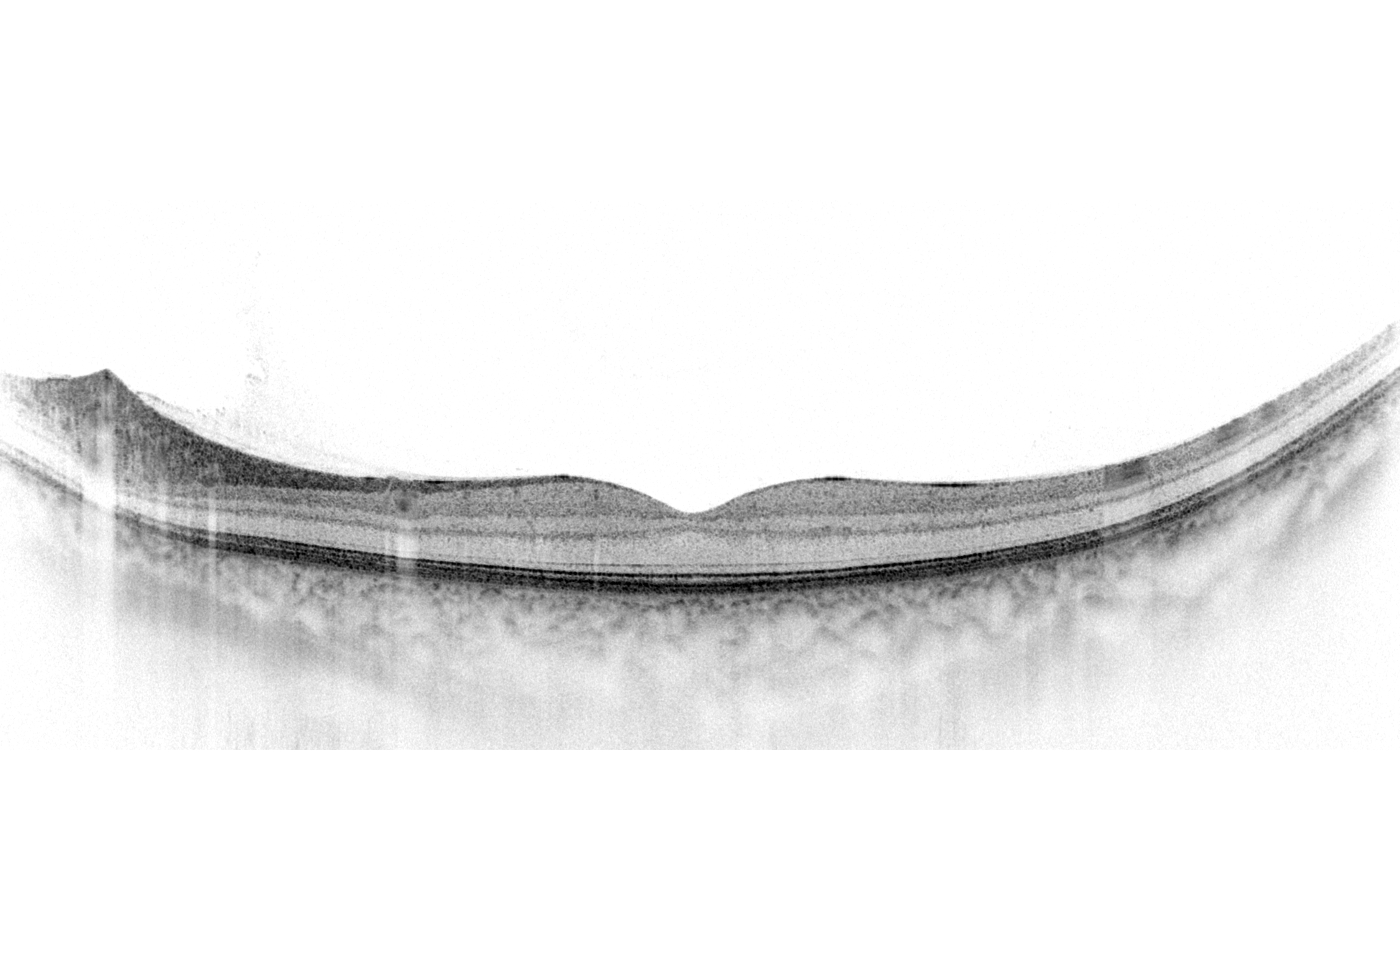

Netzhaut:

- Bis zu 12 X 12 mm Scanbereich

- 8 Layer werden automatisch erkannt

- Automatisches Follow up

- Normative Datenbanken für Nethautdicken und Ganglion Komplex